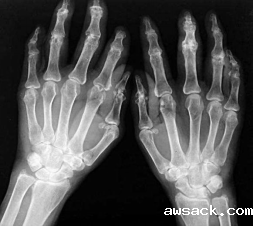

类风湿关节炎

类风湿关节炎是一种以致残性多关节滑膜炎为特征的自身免疫性疾病。主要表现为慢性、对称性、多关节、小关节炎。 侵犯关节软骨、骨和肌腱等,导致关节破坏、关节畸形和功能丧失。还可以出现发热、贫血、皮下结节及淋巴结肿大等关节外表现。

血清中常有类风湿因子、抗环瓜氨酸抗体等阳性。